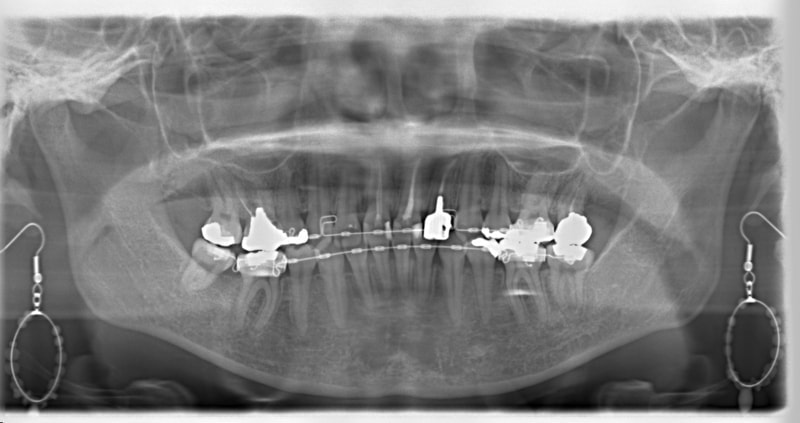

治療開始から1年8ヶ月後